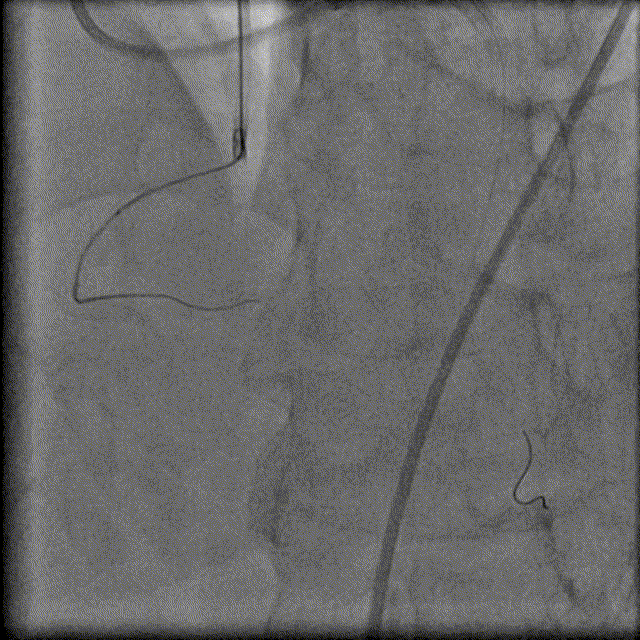

130cm Finecross微导管穿Runthrough 指引导丝到达RCA近端病变处,Fielder XTA、Pilot200指引导丝反复尝试无法通过RCA闭塞病变,随后尝试逆向侧枝开通RCA病变。

换用Instantpass微导管(170cm)支撑下送Fielder XT-R导丝通过LAD-RCA心外膜侧枝逆向通过RCA闭塞病变,推送微导管后交换Gaia Third导丝,RCA正向送Telescope™导引延长导管进行主动迎接Gaia Third导丝。